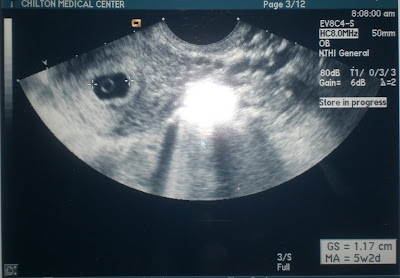

Our 1st Ultrasound Pics- Not even a little Peanut yet. Just a gestational sac, yolk sac, & most importantly a good little heartbeat! I am only five weeks! Whew, I have a long time to go. I have My first Doctors Appointment next Monday & I am Super Excited & Nervous. From the Ultrasound, It looks like a due date of May 3rd, 2009!